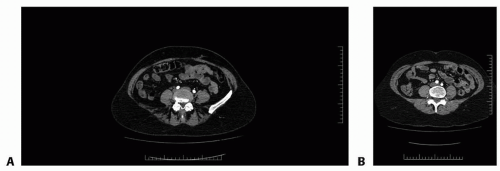

The free TRAM flap is based off the deep inferior epigastric vessels. The pedicle originates from the external iliac artery and then travels cephalad to enter the lateral and deep surface of the rectus abdominis muscle a few centimeters below the arcuate line. Just above the level of the arcuate line, the vessels typically divide into a medial and lateral row and continue superiorly, sending perforating branches through the muscle to supply the overlying skin and fat (FIG 1A,B).3,4

Three variations in DIEA branching patterns have been described, the type II variation with medial and lateral row branching being the most common at 57% to 84%. Type I vessels continue cephalad with the muscle as a single artery (27% to 29%), whereas type III vessels divide into three branches and are least common (14% to 16%).3,4,5

On average, five to six perforators originate from the DIEA.4 In a free TRAM flap, all or most of these perforators are preserved.